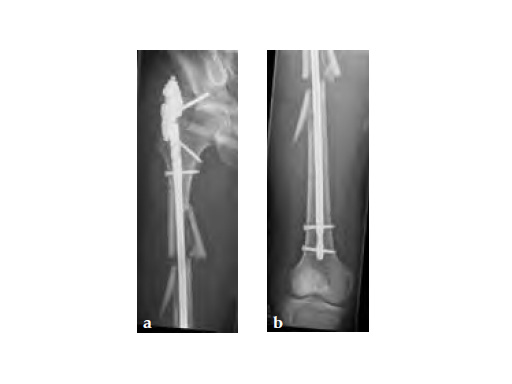

Insertion of A2FN as patient may be suffering from a stress fracture related to long term (2.5 years) bisphosphonate use. My rationale against a plate is because bisphosphonate related fractures will heal extremely slowly. In our experience even despite bone grafting union may need up to 2 years. In that time, a plate will fail in less than a year even if the patient is only allowed very minimal weight bearing.

Note despite the increased in curvature compared to other nails in the market, there is still noticeable malreduction at the fracture site (see Fig 6a-b).

Patient was allowed and achieved immediate weight bearing and in 6 weeks callus is seen at the fracture site (see Fig 7a-b).